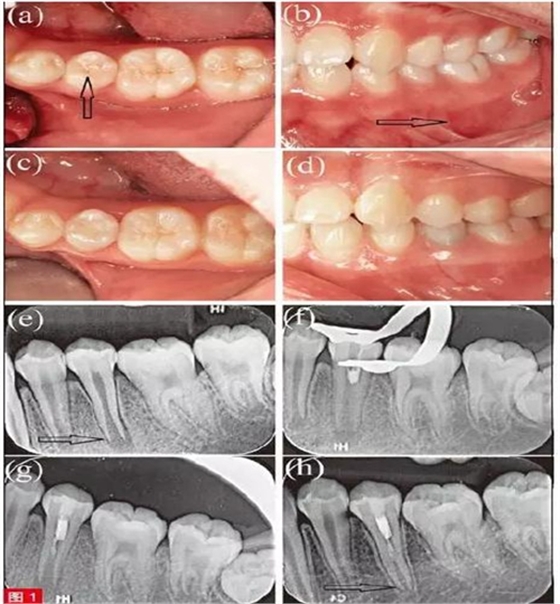

患者為10 歲男童,主訴左下后牙疼痛腫脹2周,6 個(gè)月前曾有咬物不適和冷熱刺激敏感癥狀,近兩周出現(xiàn)間斷性持續(xù)自發(fā)痛,且咬合痛明顯加重。病史由患兒本人親訴??趦?nèi)檢查,見(jiàn)左下第二前磨牙(35 牙)牙體變色,面畸形中央尖折斷,未見(jiàn)齲壞(圖1a)?;佳李a側(cè)根尖區(qū)牙齦紅腫,壓痛明顯(圖1b)。冷測(cè)和牙髓電活力測(cè)試(EPT)示35 無(wú)反應(yīng),鄰牙34、36 及對(duì)側(cè)同名牙45牙髓活力正常。35叩痛明顯,根尖區(qū)牙齦捫診有壓痛,I 度松動(dòng),牙周探診深度為2-3mm。根尖片示35 根尖孔敞開(kāi),根尖周大面積透射影(圖1e)。通過(guò)臨床和影像學(xué)檢查分析,將年輕恒牙35 診斷為有癥狀的根尖周炎。由于根尖孔敞開(kāi),牙根尚處于發(fā)育階段,考慮采用牙髓再生治療。分別告知患者及家屬應(yīng)用氫氧化鈣進(jìn)行根尖誘導(dǎo)成形術(shù)和采用牙髓再生治療的風(fēng)險(xiǎn)、并發(fā)癥、預(yù)后效果?;颊呒覍僮罱K決定采用牙髓再生治療方案,并簽署知情同意書(shū)。

首次治療中, 以4% 阿替卡因(Primacaine Adrenaline,法國(guó))局部浸潤(rùn)麻醉35 牙,橡皮障隔離后,術(shù)區(qū)消毒,高速鎢鋼車針(Diatech,瑞士)開(kāi)髓。根管不進(jìn)行機(jī)械預(yù)備,20ml 3% 次氯酸鈉溶液(NaOCl)輕柔沖洗3 分鐘,隨后,使用10ml 生理鹽水沖洗3 分鐘。沖洗液中可見(jiàn)黑色碎屑及壞死牙髓組織,此時(shí)在根管中段近冠方處可探及連續(xù)成形、仍具有活力的牙髓組織。隨即使用無(wú)菌紙尖干燥根管(Dentsply/Herpo,巴西),并待活髓組織表面形成血凝塊。將iRoot BP(Brasseler USA,美國(guó))輕輕置于血凝塊與活髓組織之上(圖1f 和1g),用3M 玻璃離子水門?。?M ESPE,德國(guó))封閉開(kāi)髓孔。告之患者及家屬術(shù)后注意事項(xiàng),保持口腔衛(wèi)生,若發(fā)現(xiàn)任何疼痛腫脹應(yīng)立即復(fù)診。

患者8 個(gè)月后復(fù)查,自述經(jīng)部分牙髓切除治療后,自發(fā)痛和牙齦腫脹癥狀逐漸減輕,該牙未再出現(xiàn)明顯不適,偶遇冰水會(huì)出現(xiàn)一過(guò)性敏感。臨床檢查,35 牙叩診及牙齦根尖區(qū)捫診均無(wú)異常,根尖片示35 根尖周組織已完全愈合(圖1c 和1d)。牙周檢查,35 松動(dòng)度和牙周探診深度均恢復(fù)正常。對(duì)35 進(jìn)行冷測(cè)和EPT 測(cè)試,顯示牙髓有活力,且EPT 數(shù)值為24,與鄰牙36的EPT 數(shù)值20 相近。根尖片示35 根尖陰影消失,根尖孔有閉合趨勢(shì)。